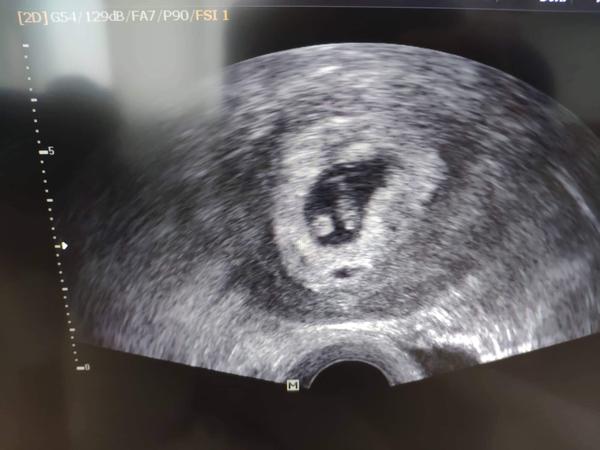

Ahoj holky, tak dalsi kontrola zamnou a vse v poradku 😍